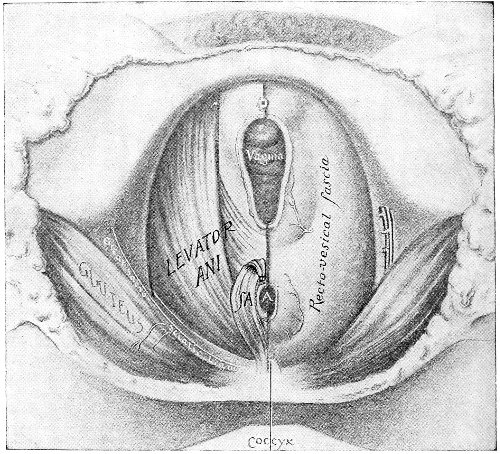

An accurate knowledge of the anatomy and mechanism of the female perineum is essential to an understanding of the nature and treatment of injuries to this structure. The anatomical structures lying between the anus behind and the symphysis pubis in front are those that most directly interest the gynecologist. Proceeding from 57 below upward, we find the following structures lying in superimposed planes: the skin, the superficial fascia, the deep layer of the superficial fascia, the transversus perinæi and the sphincter vaginæ muscles, the anterior layer of the triangular ligament, the posterior layer of the triangular ligament, the levator ani muscle (Fig. 19).

The vagina passes through these structures. They surround and support the ostium vaginæ as the fascia and muscles surround and support the opening of the rectum or the anus. The muscles and fasciæ are attached in the median line between the anus and the vagina, and therefore this part of the body, which is called the perineum, is supported or maintained in its 58 proper position by these various structures. The transversus perinæi arises from the ramus of the ischium and is inserted in the perineum. The bulbo-cavernosus, or sphincter vaginæ, arises in the perineum and is inserted in and about the clitoris. The inner fibers of the levator ani arise from the symphysis pubis and are inserted in the perineum and the lower part of the vagina (Fig. 20). When these muscles contract, their action, therefore, is to draw the perineum upward and forward. At the same time the anus is drawn upward and forward, and so also is the posterior margin of the ostium vaginæ and the lower portion of the posterior vaginal wall.

The vagina has no circular sphincter like the anus, but 59 the vaginal month is kept closed by the action of the transversus perinæi, sphincter vaginæ, and levator ani muscles, which draw the perineum forward, and thus keep the posterior vaginal wall in apposition with the anterior wall.

Fig. 21.—Muscular floor of the pelvis seen from above.

This sling of muscles and fascia, which surrounds and supports the opening of the vagina, may readily be felt in the nulliparous woman by introducing the finger in the vagina and pressing backward and outward toward the ischio-rectal fossa. We then feel plainly, immediately within the ostium vaginæ, a firm resisting band of tissue, apparently about half an inch broad, embracing the posterior portion of the lower vagina. This band is formed by the inner edges of the various muscles and planes of fascia that have been described.